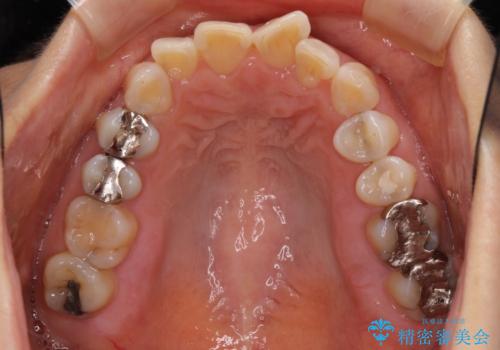

- 前歯のデコボコと上下正中のずれを気にして来院された患者様です。

下顎骨が骨格的にずれがあったため、しっかりと正中を合わせるとなるとワイヤー矯正が必要でしたが、マウスピース矯正を希望されたため、極力正中を合わせることを目標に、インビザラインにて矯正治療を行うこととしました。